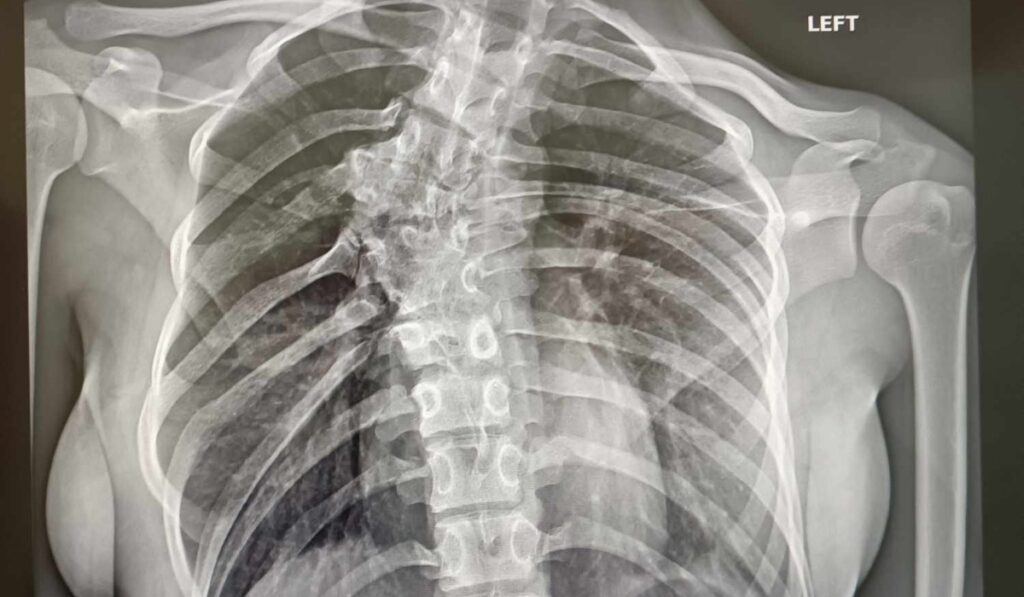

A 13 éves nevetlenfalui Kincses Valentinánál súlyos gerincferdülést, többszörös fejlődési zavart, félcsigolya-képződést, illetve lokális blokkot diagnosztizáltak bordadeformitással és borda összenövéssel – számolt be róla közösségi oldalán a kislány édesanyja, Kincses Diána.